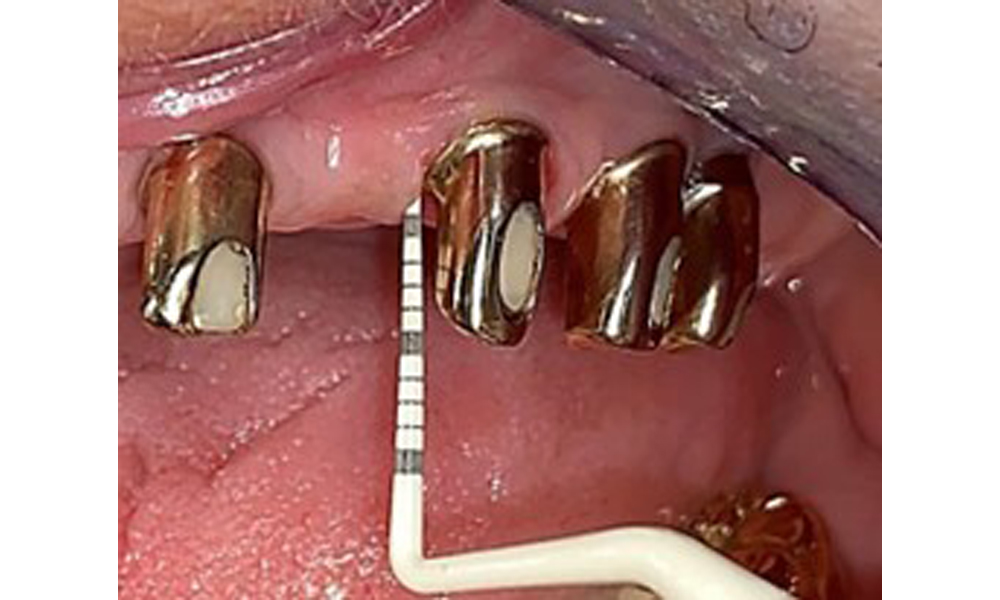

Die Patientin wurde vor über 25 Jahren mit einer kombinierten herausnehmbare Implantat-Teleskopprothese im Oberkiefer versorgt (Abb. 1, Abb. 2, Abb. 3) und ist sehr glücklich über ihren Zahnersatz. Im Unterkiefer hat die Patientin einen suffizienten festsitzenden Zahnersatz. (Abb. 4)

Der dentale Befund stellt sich wie folgt dar: Kombinierte herausnehmbare Implantat- und zahngetragene Teleskoparbeit auf Implantaten 15, 13, 21, 23, 24, 25 und Zahn 11 (Abb. 1, Abb. 2, Abb. 3). Im Unterkiefer ist die Patientin mit einem festsitzenden Zahnersatz versorgt. 37–34 sowie 45–47 haben suffiziente Brücken (Abb. 4). Kronenränder sind intakt, aktive kariöse Läsionen sind nicht vorhanden. An Zahn 43 zeigt sich eine Compositefüllung mit Randspalt. Im Unterkiefer liegen Rezessionen mit freiliegender Wurzeloberfläche zwischen 1 – 3 mm vor. Dies trifft auch für 11 zu.